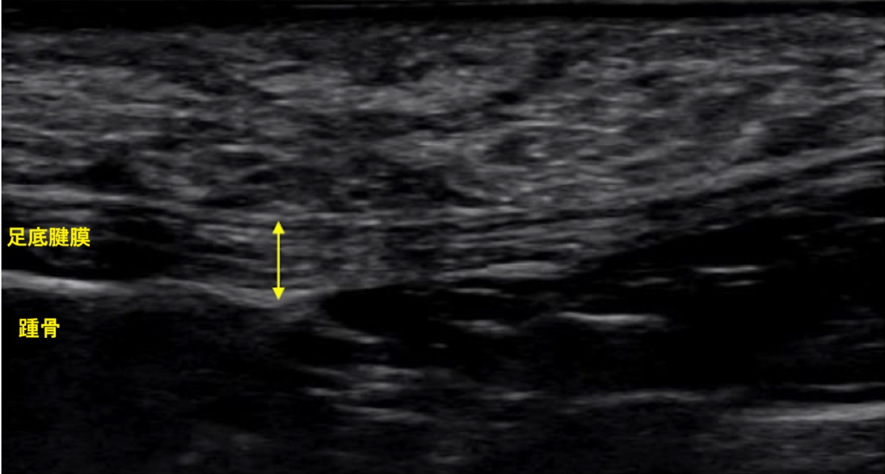

続いて超音波(エコー)検査を行ったところ、足底腱膜(そくていけんまく)という足の裏にある組織の腫れを確認しました。

上記の所見から足底腱膜炎と診断しました。